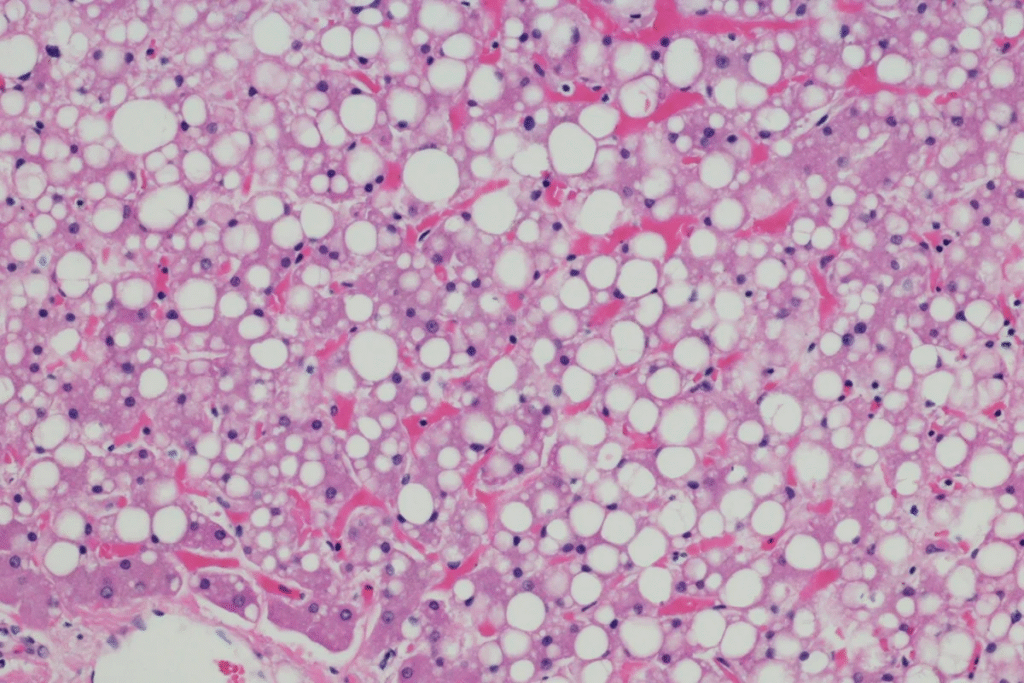

Uma condição cada vez mais comum, a esteatose hepática, conhecida como gordura no fígado, é uma doença de estilo de vida. Desencadeado por obesidade, má alimentação, sedentarismo e excesso de álcool, o acúmulo excessivo de gordura nas células hepáticas é preocupante e pode causar problemas sérios de saúde, como cirrose e até câncer.